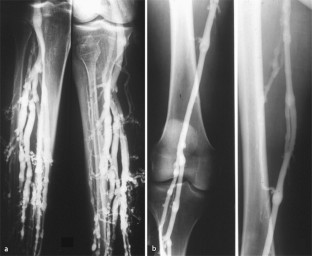

Abb. 4

Abb. 5